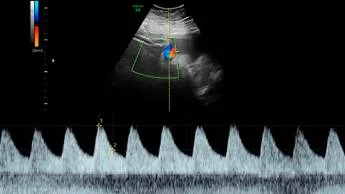

Существует два основных режима проведения допплер УЗИ — это дуплексное и триплексное сканирование. В первом случае у специалиста есть возможность оценить структуру сосудов, а также скорость кровотока. Триплексное сканирование считается более точным и информативным, поскольку позволяет дополнительно получить цветное изображение.

- Режим цветового картирования — кодировка скорости кровообращения на разных участках при помощи цвета. Таким образом, на мониторе врач видит сосуды с разной скоростью кровотока.

В ходе диагностики специалист оценивает несколько параметров, в частности, индекс сопротивления артерий пуповины и матки. Полученные результаты врач сопоставляет с нормальными данными, после чего делает заключение. Примечательно, что отклонения от нормы не всегда говорят о патологиях развития плода или риске преждевременных родов.